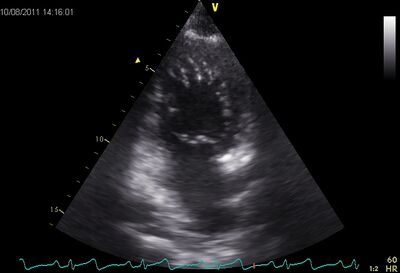

Asym.cmp1.jpg

Asymmetric hypertrophy